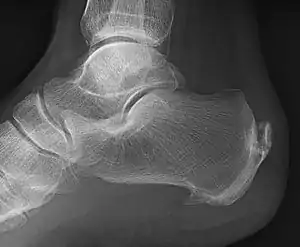

A radiograph showing osteophytes on the posterior and inferior aspects of the calcaneus | |

When a foot is exposed to constant stress, calcium deposits build up on the bottom of the heel bone. However, repeated damage can cause these deposits to pile up on each other, causing a spur-shaped deformity, called a calcaneal (or heel) spur.[2] It is typically detected by x-ray.[3] It is a form of exostosis.

An inferior calcaneal spur is located on the inferior aspect of the calcaneus and is typically a response to plantar fasciitis over a period, but may also be associated with ankylosing spondylitis (typically in children). A posterior calcaneal spur develops on the back of the heel at the insertion of the Achilles tendon.[2]

An inferior calcaneal spur consists of a calcification of the calcaneus, which lies superior to the plantar fascia at the insertion of the plantar fascia. A posterior calcaneal spur is often large and palpable through the skin and may need to be removed as part of the treatment of insertional Achilles tendonitis.[2]

Spur outgrowths can be detected through physical exam followed by a lateral foot x-ray.